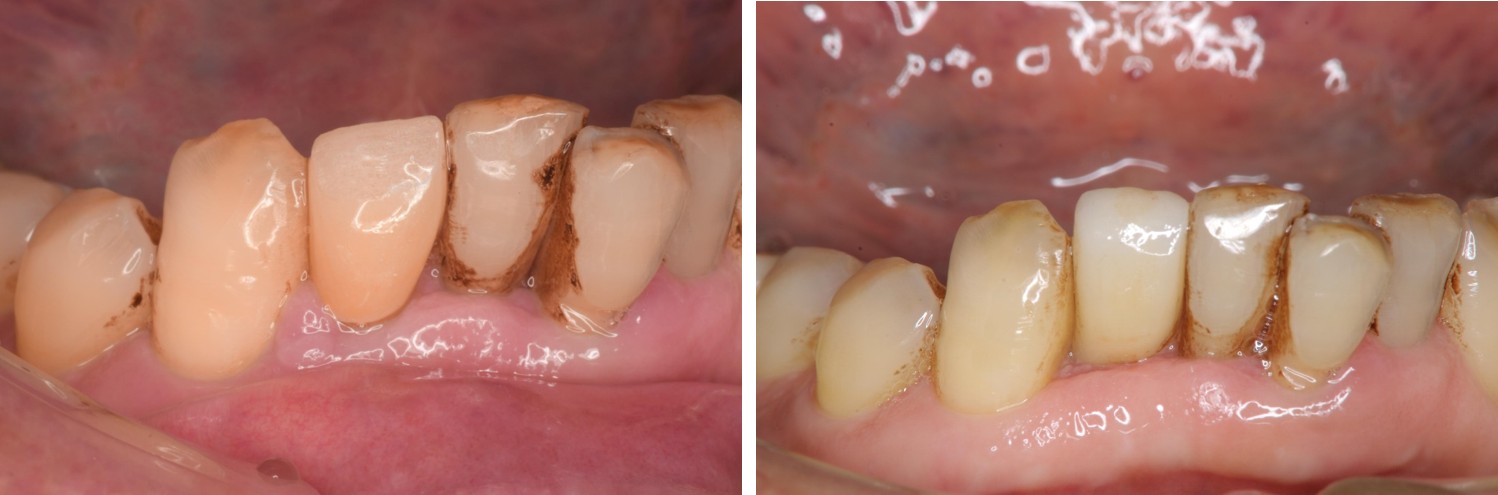

治療前,右下側門牙嚴重牙周病

治療後,咬合牙周適應良好

治療後,密合度良好

術前、術後比較